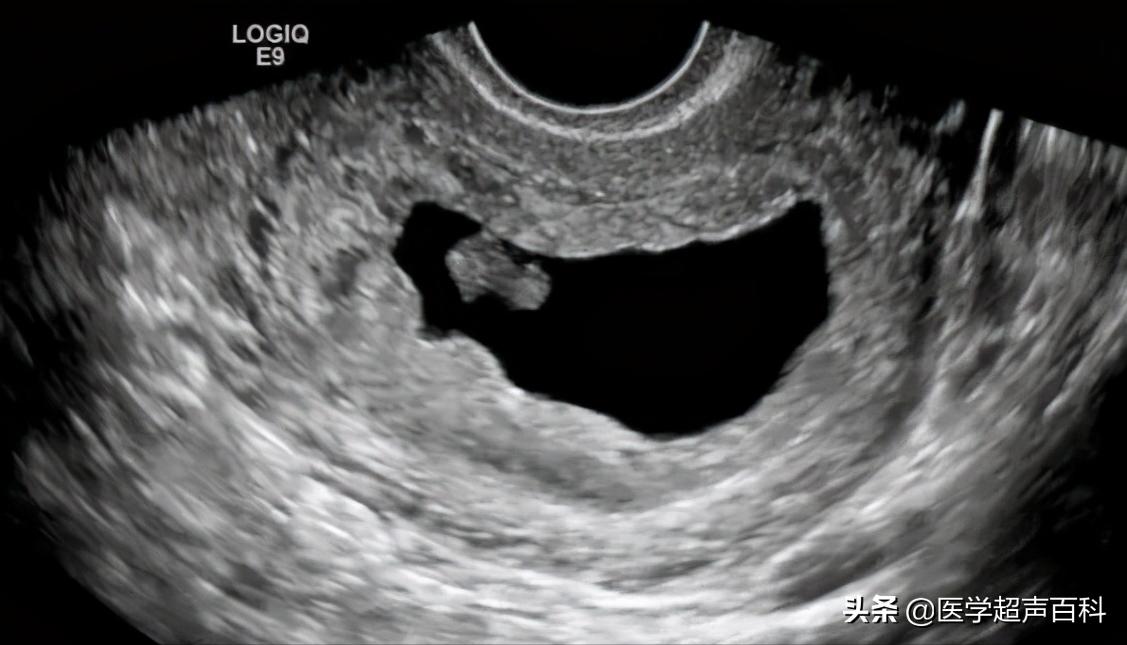

2、有胚芽无胎心B超示妊娠囊内可见胚芽,但无胎心搏动。

3、有胎心后停育是指B超在动态监测妊娠囊,可以先有胎芽胎心搏动,待一段时间 B超又未监测到胎心搏动,只见枯萎的妊娠囊。

经阴道超声

1、胚胎长度≤5mm,无心管搏动,7-10天后复查仍无心管搏动。

2、胚胎长度>5mm,无心管搏动或妊娠囊平均内径>20mm,无卵黄囊及胚胎。

3、妊娠囊平均内径≤20mm,无卵黄囊及胚胎,1-2周后复查仍无卵黄囊及胚胎。

可见胚胎停育是B超医生的描述术语,因为通过B超可以非常直观地看到正常胚胎的胎心搏动和胚胎停育中的无胎心搏动,因为通俗易懂,被患者及医生广泛接受。